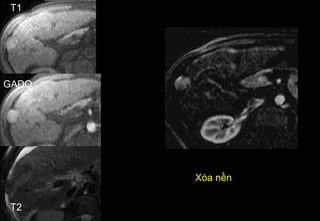

Hopital CROIX ROUSSE

Xóa nền

T1

GADO

T2